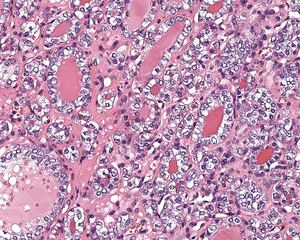

يُظهر ورم NIFTP سمات نووية محددة لسرطان الغدة الدرقية الحليمي.

السمات النووية لسرطان الغدة الدرقية الحليمي ، ولكن داخل ورم مغلف: NIFTP

4) يجب أن يتمتع بالسمات النووية المميزة لسرطان الغدة الدرقية الحليمي ، على الرغم من أنه في بعض الأحيان تكون السمات غير منتظمة في التوزيع دون أن يظهر الورم هذه السمات. يمكن تقسيم الميزات النووية إلى ثلاث فئات رئيسية:

• الحجم والشكل النوويان : التوسيع النووي ، والاستطالة النووية ، والتداخل والازدحام النووي. يعد فقدان القطبية النووية ، مع وجود نوى في المنطقة التجويف أو الوسطى أو القاعدية للخلايا اكتشافًا مفيدًا أيضًا.

• الانحرافات في الأغشية النووية : ملامح نووية غير منتظمة ، أخاديد وطيات نووية ، "عضات الفئران" أو تكوينات نصفية هلالية ، ووجود مشتملات هيولية داخل النواة.

• خصائص الكروماتين النووي: تنقية الكروماتين النووي ، غالبًا مع التكثيف أو التهامش على طول الأغشية النووية ، مما ينتج عنه هوامش نووية بارزة ، أو نوى زجاجية ، أو كروماتين نووي ناعم ، وحتى غباري.